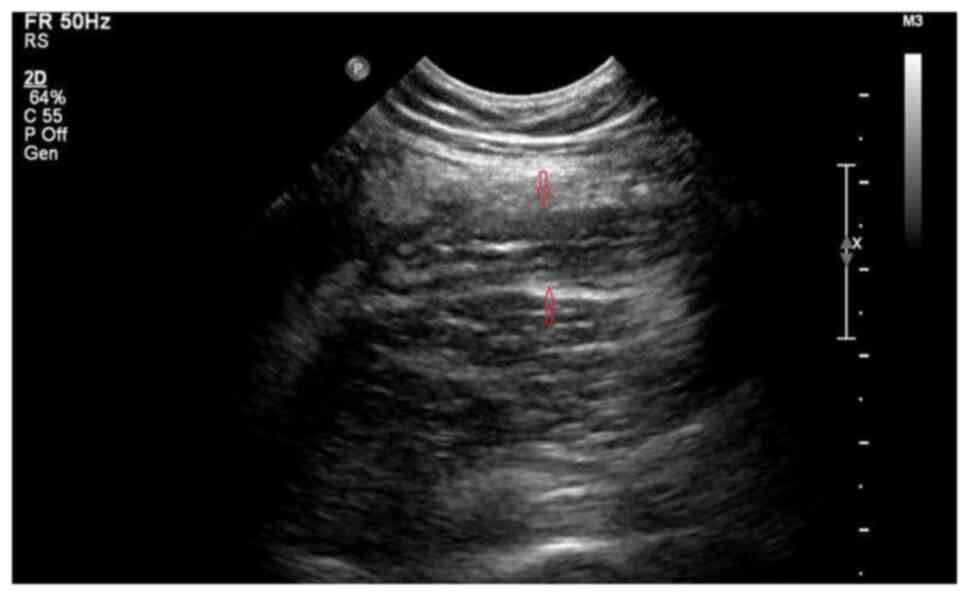

Figure 1

Abdominal ultrasound showing acutely inflamed appendix, as indicated by the arrows.

A 13-year-old female adolescent individual with pain in the lower right abdomen for 3 days was first admitted to Shanghai Children's Hospital (Shanghai, China). She initially complained of pain in the lower right abdomen but without fever or diarrhea 3 days before admission. However, she vomited once 1 day before admission. No similar type of abdominal pain was experienced by the patient in the past. Physical examination revealed a fixed area of tenderness in the lower right abdomen without rebound tenderness. No obvious masses could be found in the abdominal area and the bowel sound was normal. Laboratory examination revealed her inflammatory markers to be elevated. Specifically, the white blood cell count was 8.49x109 cells/l and C reactive protein (CRP) count was 15 mg/l. The blood biochemical parameters of liver function, renal function and electrolytes were normal. In addition, abdominal ultrasound revealed that the diameter of the appendix was 9 mm, suggesting an acutely inflamed appendix (Fig. 1). From the computerized tomography (CT) scan images it could be observed that the appendix was thickened with exudation, where there was a small quantity of fluid within the pelvic cavity (Fig. 2).